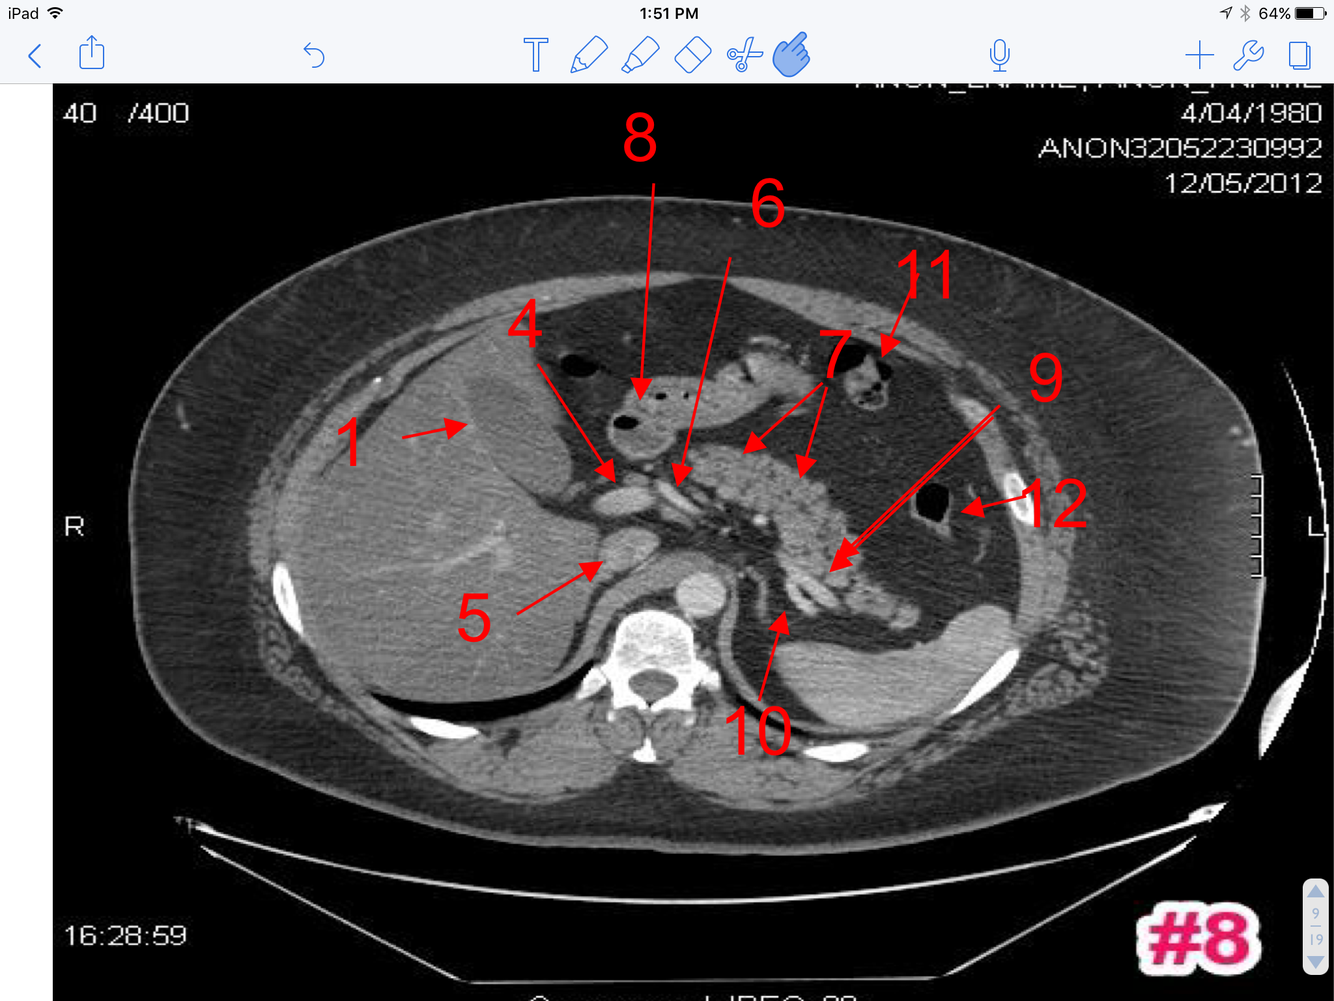

10

Q

A

1. Lt Adrenal Gland

2. Splenic Artery

3. Celiac axis (trunk)

4. Rt. Adrenal

11

1. Fundus of the gallbladder

2. Uncinate process of pancreas

3. Portal Vein

4. Splenic Vein

5. Upper Pole of Lt Kidney

6. Superior mesenteric artery